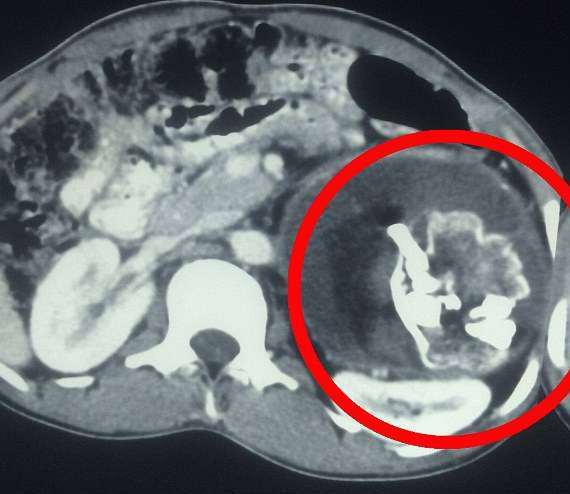

▼医生通过X光检测,发现他体内存在异物。

库马尔到医院检查时,医生为他做了X光检测,发现他的体内藏有一个2.5公斤重的异物。大家都以为这是个肿瘤,但手术时却看到异物上有牙齿,还有很多毛髮。医生确定这是一个「胎中胎」,已经在库马尔的体内寄生了18年。

▼异物是个发育不完全的头颅,上面有头髮和牙齿。